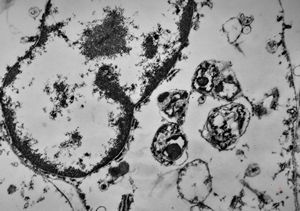

F,50y. | progressive multifocal leukoencephalopathy- viral particles in a glial cell